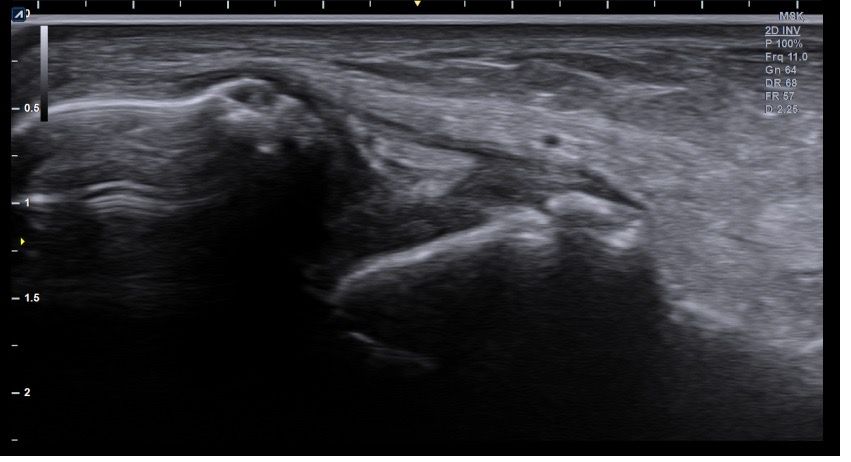

복숭아뼈 미세골절 초음파 사진 관련 질문

발목 접지른 후 치료받는 중인데요 복숭아뼈 미세골절이라고 하셨네요 3월 1일 다친뒤네 3월7일 병원방문후에 위에 초음파랑 엑스레이 촬영했고요 그뒤 반깁스 중입니다. 위에 엑스레이 상에선 안나오는데 초음파 사진에선 미세골절이 맞을까요? 골절이 경미한 수준인지 아니면 중한 건지 궁금합니다 그리고 다음주에 병원 방문 후 초음파 또 촬영하기로 했는데 그때 반깁스도 풀 수 있을까요??

미세골절 같은 경우 엑스레이서 잘 안 보일 수 있고 초음파에서 연부조직과 뼈의 상태를 좀 더 세밀하게 확인하여 확인할 수 있습니다. 미세골절이 경미한 수준이라면 초음파를 통해서 확인이 가능하며 치료 진행 상황에 따라 반깁스를 푸는 시점은 달라질수 있습니다.

발목의 복숭아뼈에 미세골절이 의심되는 경우, 엑스레이에서는 미세골절이 잘 보이지 않을 수 있습니다. 엑스레이는 큰 골절을 잘 확인하지만, 미세한 골절이나 염증 반응은 잘 나타나지 않기 때문이죠. 초음파는 조직의 변화를 보다 민감하게 감지할 수 있기 때문에, 미세골절을 발견하는 데 도움을 줄 수 있습니다. 초음파에서 미세골절이 확인되었다면, 이는 경미한 골절일 가능성이 높아요. 하지만 골절의 정확한 상태나 치유 과정을 판단하려면 정밀 검사가 필요하죠